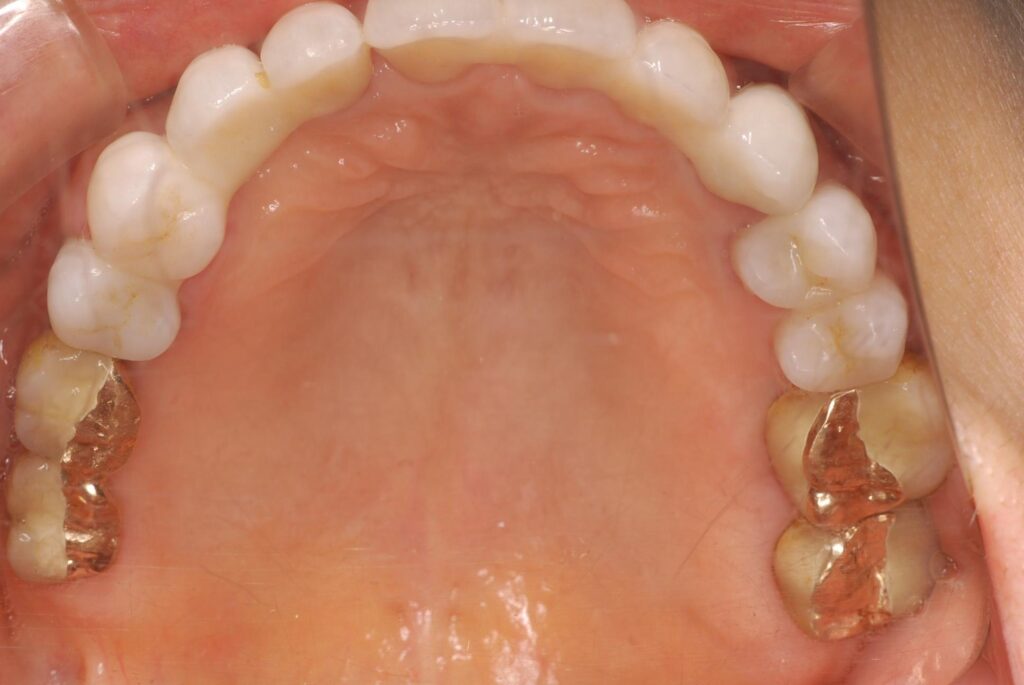

20年前、重度の歯周病で歯を失い、インプラント治療を行った患者さんのケースです。治療後は定期メンテナンスを欠かさず、ご自身でも丁寧なセルフケアを続けてこられました。

その結果、骨の吸収も minimal で、インプラント体(フィクスチャー)は20年経っても非常に安定しています。

20年安定している症例は例外なく、治療前の歯周病コントロールと定期健診が徹底されています。